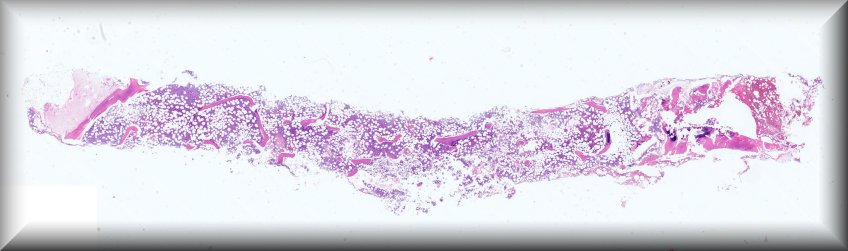

Caso 10.- Juan Díaz Nohales; Omérim Gaona Juárez; Nuria Rausell Fontestad; Javier Furriol Collado; María Soraya Hernández Girón; Empar Mayordomo Aranda.

Hospital Universitario y Politécnico La Fe. Valencia.

Paciente masculino de 82 años acude a urgencias por presencia de escalofríos y fiebre de 2 meses de evolución, con picos de hasta 39ºC. Asocia además astenia y anorexia de hasta 12 kilos durante estos meses con debilidad generalizada y alteración de la marcha, así como caídas frecuentes. En la TAC-tap se observa una esplenomegalia globulosa. Se lleva a cabo biopsia de médula ósea para estudio anatomopatológico.